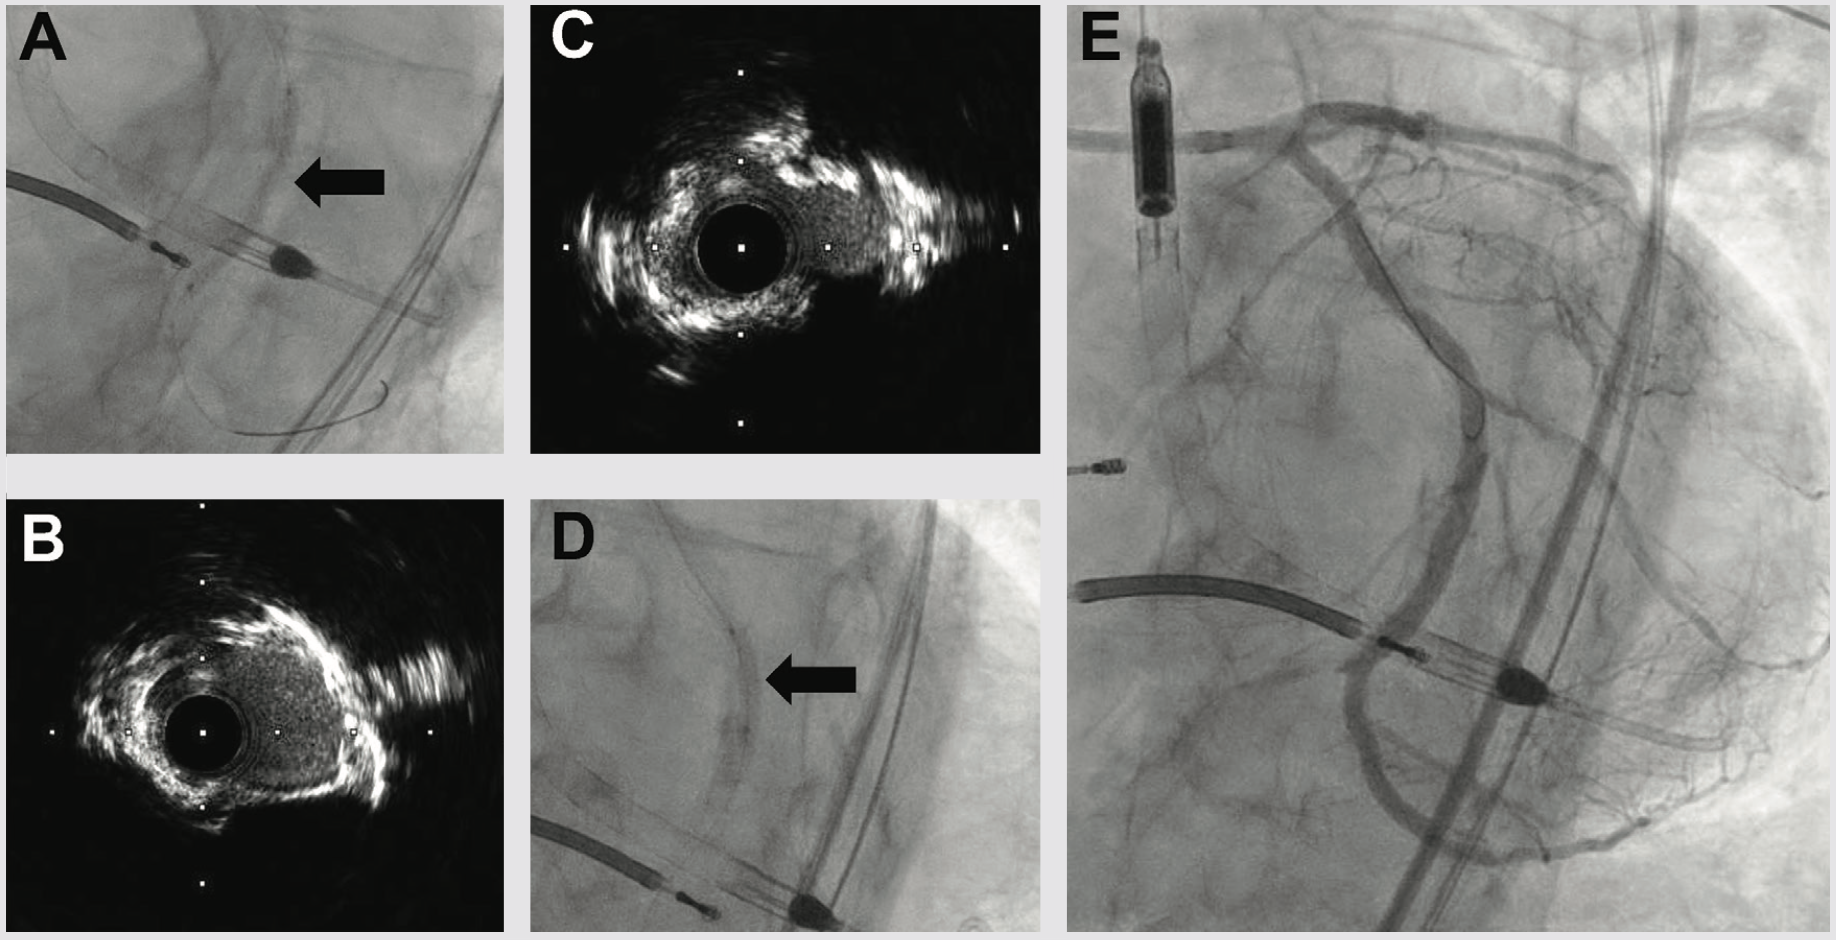

Three weeks later, we performed LAD CTO PCI. The LVEF had improved to 35%, and the patient was euvolemic and hemodynamically well compensated. Right radial occlusion and left radial vasospasm prevented 7 Fr radial access, so we re-accessed the LCFA, where angiography showed a widely patent iliac Shockwave treatment zone from the prior case. Using a 7 Fr system, diagnostic angiography demonstrated patency of the LCX, LPDA, and OM1 treatment sites. We next utilized an AWE strategy to address the LAD CTO (Figure 4). CTO wires immediately tracked subintimal and using a Mongo wire, we used mini-subintimal tracking and antegrade reentry (STAR) to reenter the LAD with <20 mm subintimal distance (Figure 4). Initial noncompliant balloons would not expand completely. IVUS showed (1) severe circumferential and nodular calcium in the proximal and mid LAD, and (2) limited (<20 mm) subintimal tracking before luminal reentry. We treated with a 3.5 mm Shockwave balloon to modify the calcium compliance to facilitate optimal stent expansion. After additional predilation with 1-to-1 sized noncompliant balloons, we placed overlapping stents, post dilated under IVUS guidance, and achieved excellent IVUS and angiographic results (Figure 4). The patient was discharged the following day, and on follow-up has had complete resolution of angina and no further heart failure exacerbations. Intravascular imaging identifies calcified stenoses that restrict stent expansion and reduce the durability of PCI revascularization. Shockwave intravascular lithotripsy improves the compliance of calcified stenoses to facilitate optimal expansion, with the goal of improving short- and long-term stent patency.